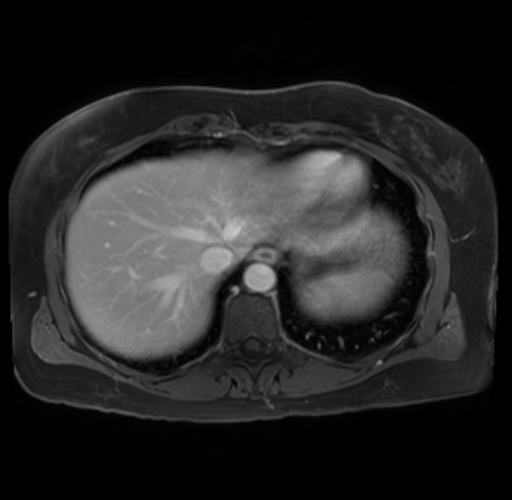

Imaging Analysis

Look through the patient's CT scan to identify any areas of concern for the necessary procedure.

Based on your CT findings, which issue(s) are present and would give reason for "planned slowing down moment(s)" in this case?